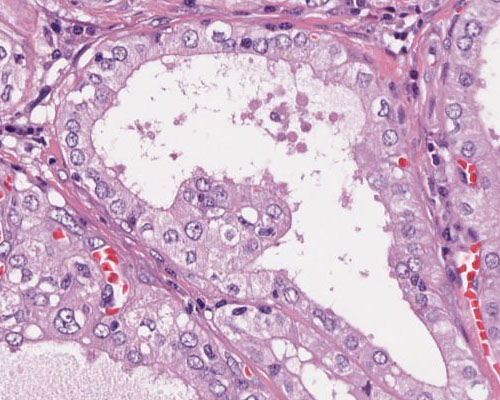

A86 Prostatahyperplasie

Vergrößerte, unterschiedlich weite Drüsen mit doppelreihigem Epithel

-

Verbreiterung der glatten Muskulatur und des Stromas